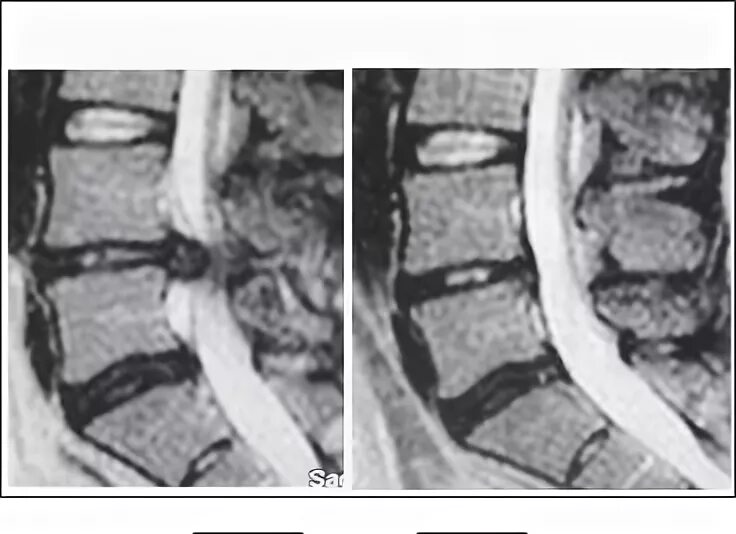

Диффузная грыжа l4 l5